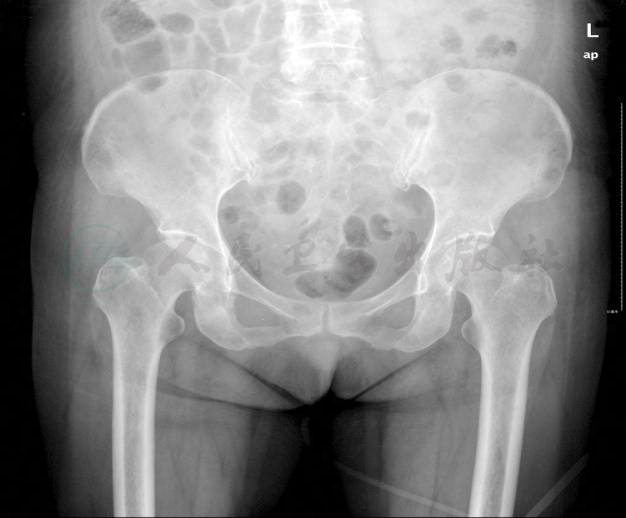

骨盆X线片:骨盆多发虫蚀状骨质破坏改变(图4)。

图4 骨盆X线片

患者以腹痛、血尿淀粉酶水平升高为特点入院,初诊首先应想到急性胰腺炎,但该患者血脂肪酶不高,影像学表现缺乏典型的急性胰腺炎征象,并且临床针对急性胰腺炎的治疗未见明显效果,因此可排除急性胰腺炎的可能。入院后查体及辅助检查进一步排除了胃肠道穿孔、胆囊炎等可导致血淀粉酶轻中度升高的急腹症。同时,患者无明显腮腺区疼痛或肿胀,结合腮腺B超结果,可排除腮腺疾病导致淀粉酶水平升高。患者血清淀粉酶升高的同时,尿淀粉酶也显著增高,不符合巨淀粉酶血症的特点。另外,患者肾功能正常,排除了因肾小球滤过率下降而导致的高淀粉酶血症。综合以上资料,考虑该病例为肿瘤细胞合成分泌淀粉酶所致的高淀粉酶血症。患者腹部CT提示多发骨质破坏,但未见明显实体肿瘤,结合血IgG及血、尿λ轻链升高,头颅CT、骨盆X线片多部位骨质破坏,高度提示多发性骨髓瘤可能,随后的骨髓穿刺活检结果确诊了多发性骨髓瘤。